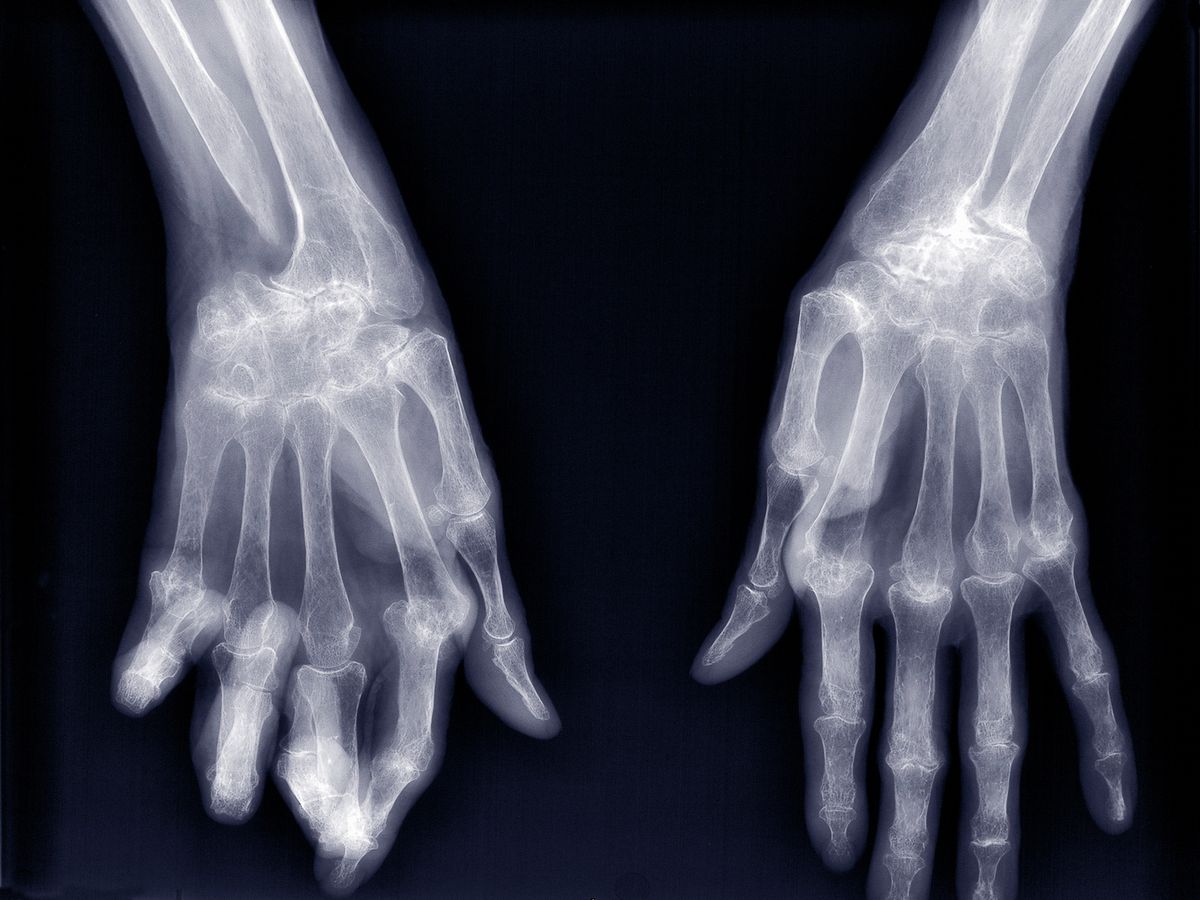

Ամանորը հայերիս ամենասիրելի տոներից է։ Ինչպես գիտենք, Նոր տարվա գիշերվա (իսկ վերջին տարիներին՝ ոչ միայն այդ գիշերվա) գլխավոր խորհրդանիշներից են նաև պայթուցիկներն ու տարատեսակ պիրոտեխնիկան։ Քանի որ դրանով զբաղվում են հիմնականում երեխաները, հորդորում ենք ծնողներին ուշադիր լինել․ այս տարի արդեն գրանցվել է պայթուցիկից երեխայի վնասման առաջին դեպքը։ Օրերս 10֊ամյա փոքրիկը չի հասցրել ժամանակին ձեռքից գցել «բոմբը», այն պայթել է և կտրել նրա մատները։ Ներքևի նկարում ներկայացված է օրինակ, թե ինչ տեսք է ստանում վնասված ձեռքը։

Տեղափոխվելով «Սուրբ Աստվածամայր» ԲԿ երեխան վիրահատվել է՝ աջ դաստակի առաջին, երկրորդ մատները անդամահատվել են, մյուս մատները բժիշկներին հաջողվել է պահպանել: